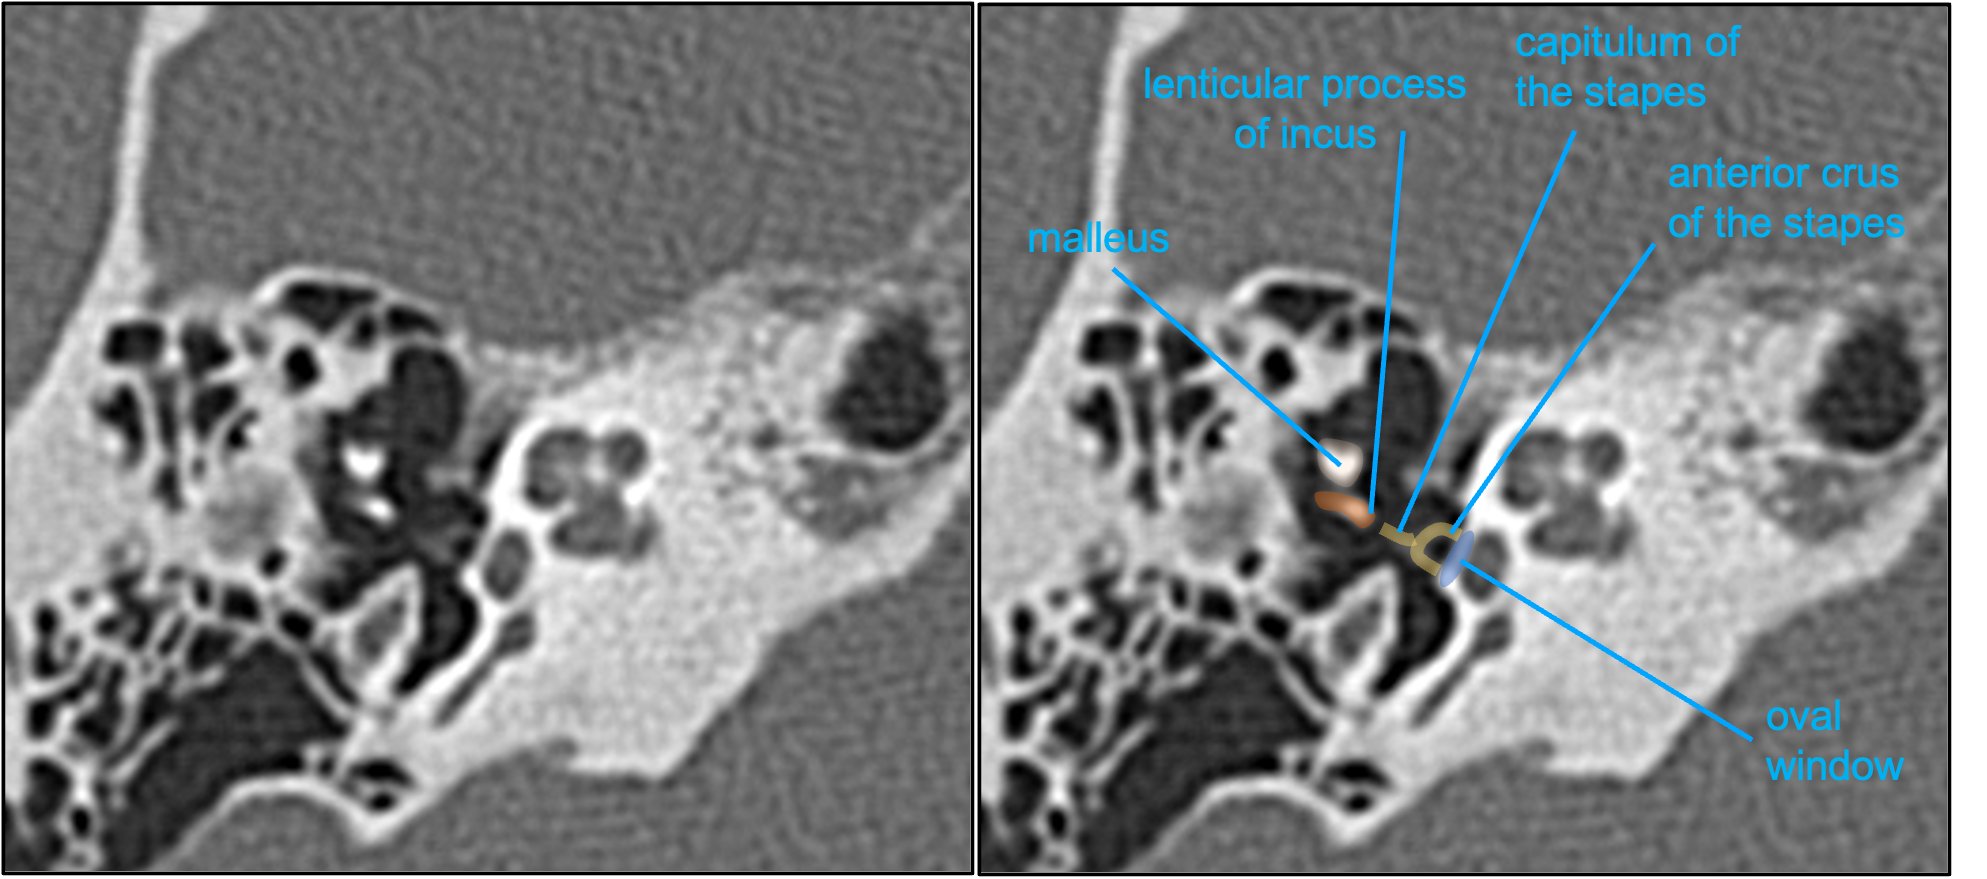

Aaron Rutman, MD on Twitter "The lenticular process articulates w/ the Medical Term Of Stapes Stapedes) is the smallest and most medial of the three middle ear ossicles. the stapes (plural: Located in the middle ear, the stapes is the smallest bone in the human body. stapes, also known as the stirrup bone, is one of the three ear ossicles found in the middle ear, besides the incus. the stapes is one. Medical Term Of Stapes.

Fixed stapes footplate appears normal on CT aside from associated Medical Term Of Stapes The most lateral and largest of the auditory. Noun [ c usually singular ]. the stapes (plural: stapes, also known as the stirrup bone, is one of the three ear ossicles found in the middle ear, besides the incus. Located in the middle ear, the stapes is the smallest bone in the human body. Stapedes) is the smallest. Medical Term Of Stapes.

Fig 3. Surgical and Clinical Confirmation of Temporal Bone CT Medical Term Of Stapes Meaning of stapes in english. stapes, also known as the stirrup bone, is one of the three ear ossicles found in the middle ear, besides the incus. The most lateral and largest of the auditory. Stapedes) is the smallest and most medial of the three middle ear ossicles. the stapes is one of three bones of the middle. Medical Term Of Stapes.